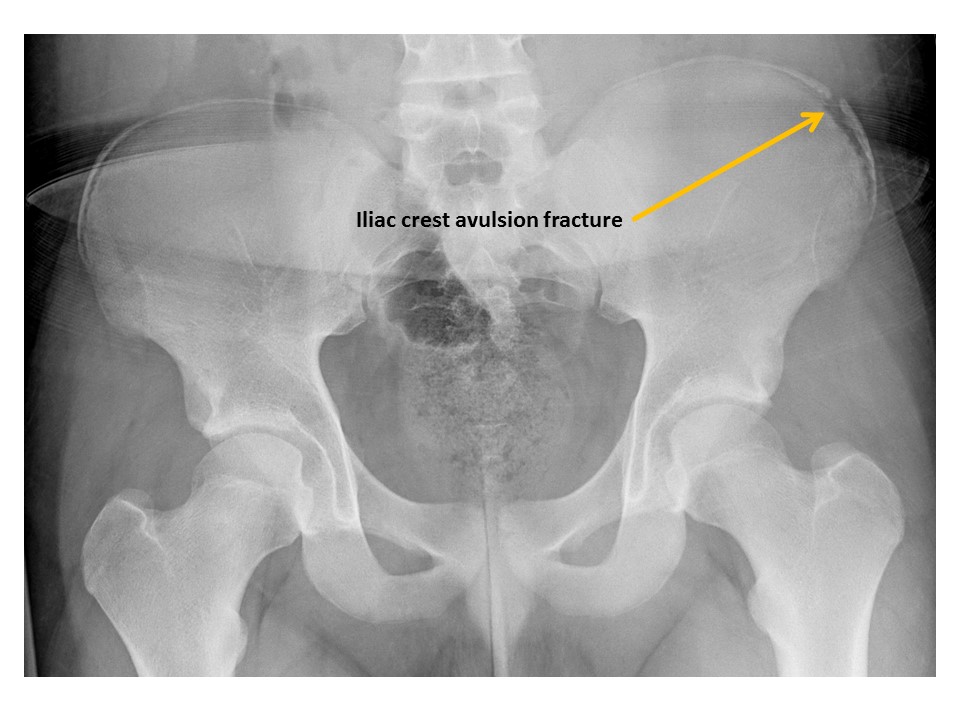

Iliac crest avulsion fractures are present. [Yes/No]